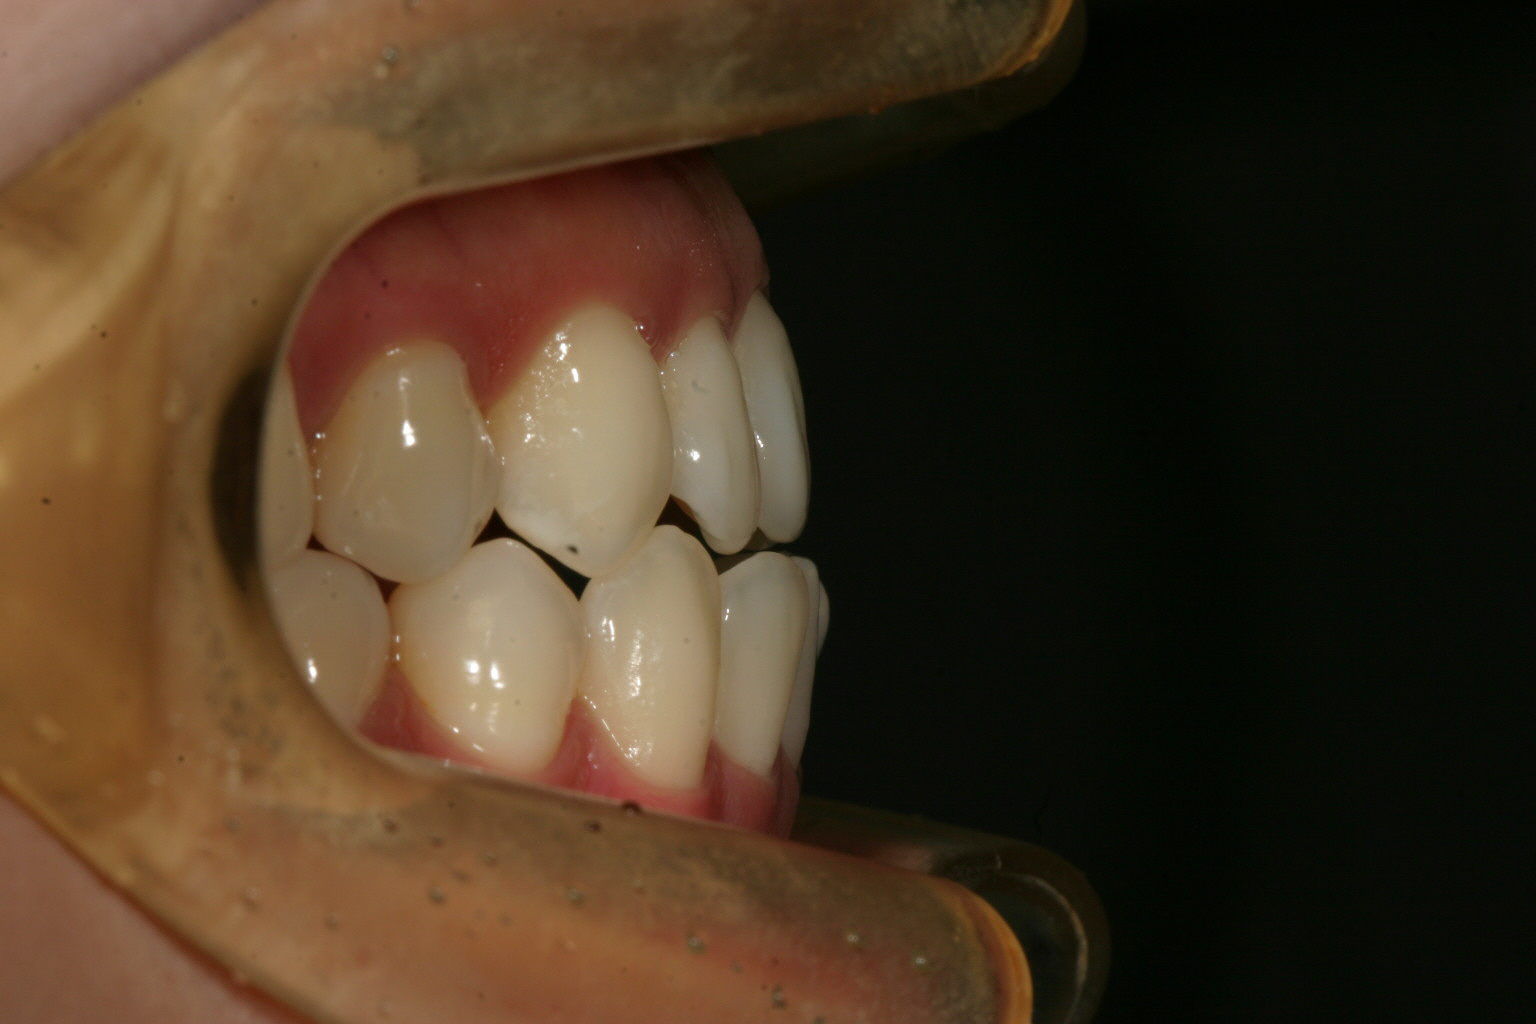

綺麗な被蓋関係に改善されました。

今回の症例ではインビザライン矯正で得意とする手法でIPRって事メインに行いました。IPRと言う方法は上下の歯と歯の間を少し削り上下の歯のバランスを変えると言う方法です。(最大でも隙間に0.5mm程です。)

下顎の歯の隙間を沢山削り上顎は少し削って全体的にアーチを締め付ける事により下顎のアーチを小さくして上顎より内方に入れ、上顎前歯を少し下に下げれば綺麗な被蓋関係が出来上がります。